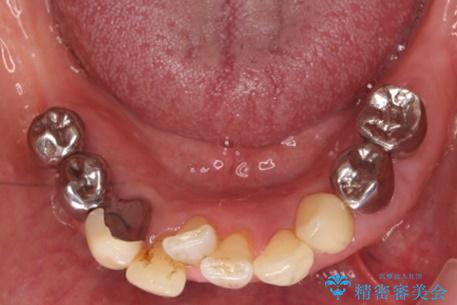

- 下の前歯(左下2)と奥歯の動揺がひどくなってきたことを主訴に来院された患者様です。

精査したところ、前歯の咬み合わせが反対になっていること、下の奥歯(下顎両側67)が4本欠損していることから動揺が生じていました。

入れ歯も抵抗があるとのことから、相談を重ね、今の状態では保存不可能な下の前歯(左下2)を抜去し、ブリッジや連結補綴により動揺を抑えることにしました。

下顎大臼歯が欠損したままで今ある歯に負担がかかりやすいことから、長期的予後は保証できないことをご理解頂いた上で治療を行いました。